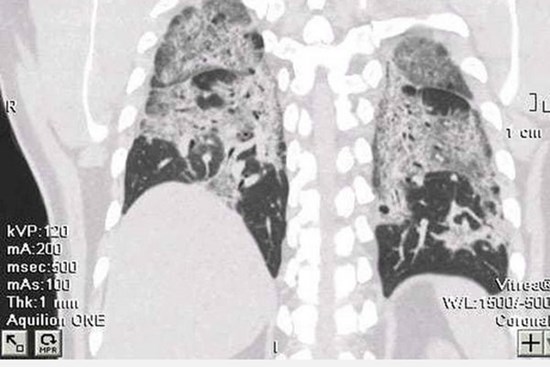

F0 không có triệu chứng, phổi vẫn trắng xoá hậu Covid-19

Xơ phổi là bệnh lý nguy hiểm của hậu Covid-19, dù không nhiều nhưng nói tới xơ phổi sau Covid bác sĩ cũng thấy “lo lo”.